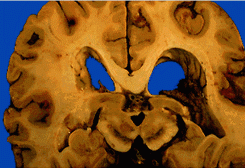

•Coronal section of an atrophic brain with markedly enlarged ventricles characteristic of Alzheimer's disease but also of other dementias.

(Description By:Margaret Grunnet, M.D. )

(Image Contrib. by: UCHC )